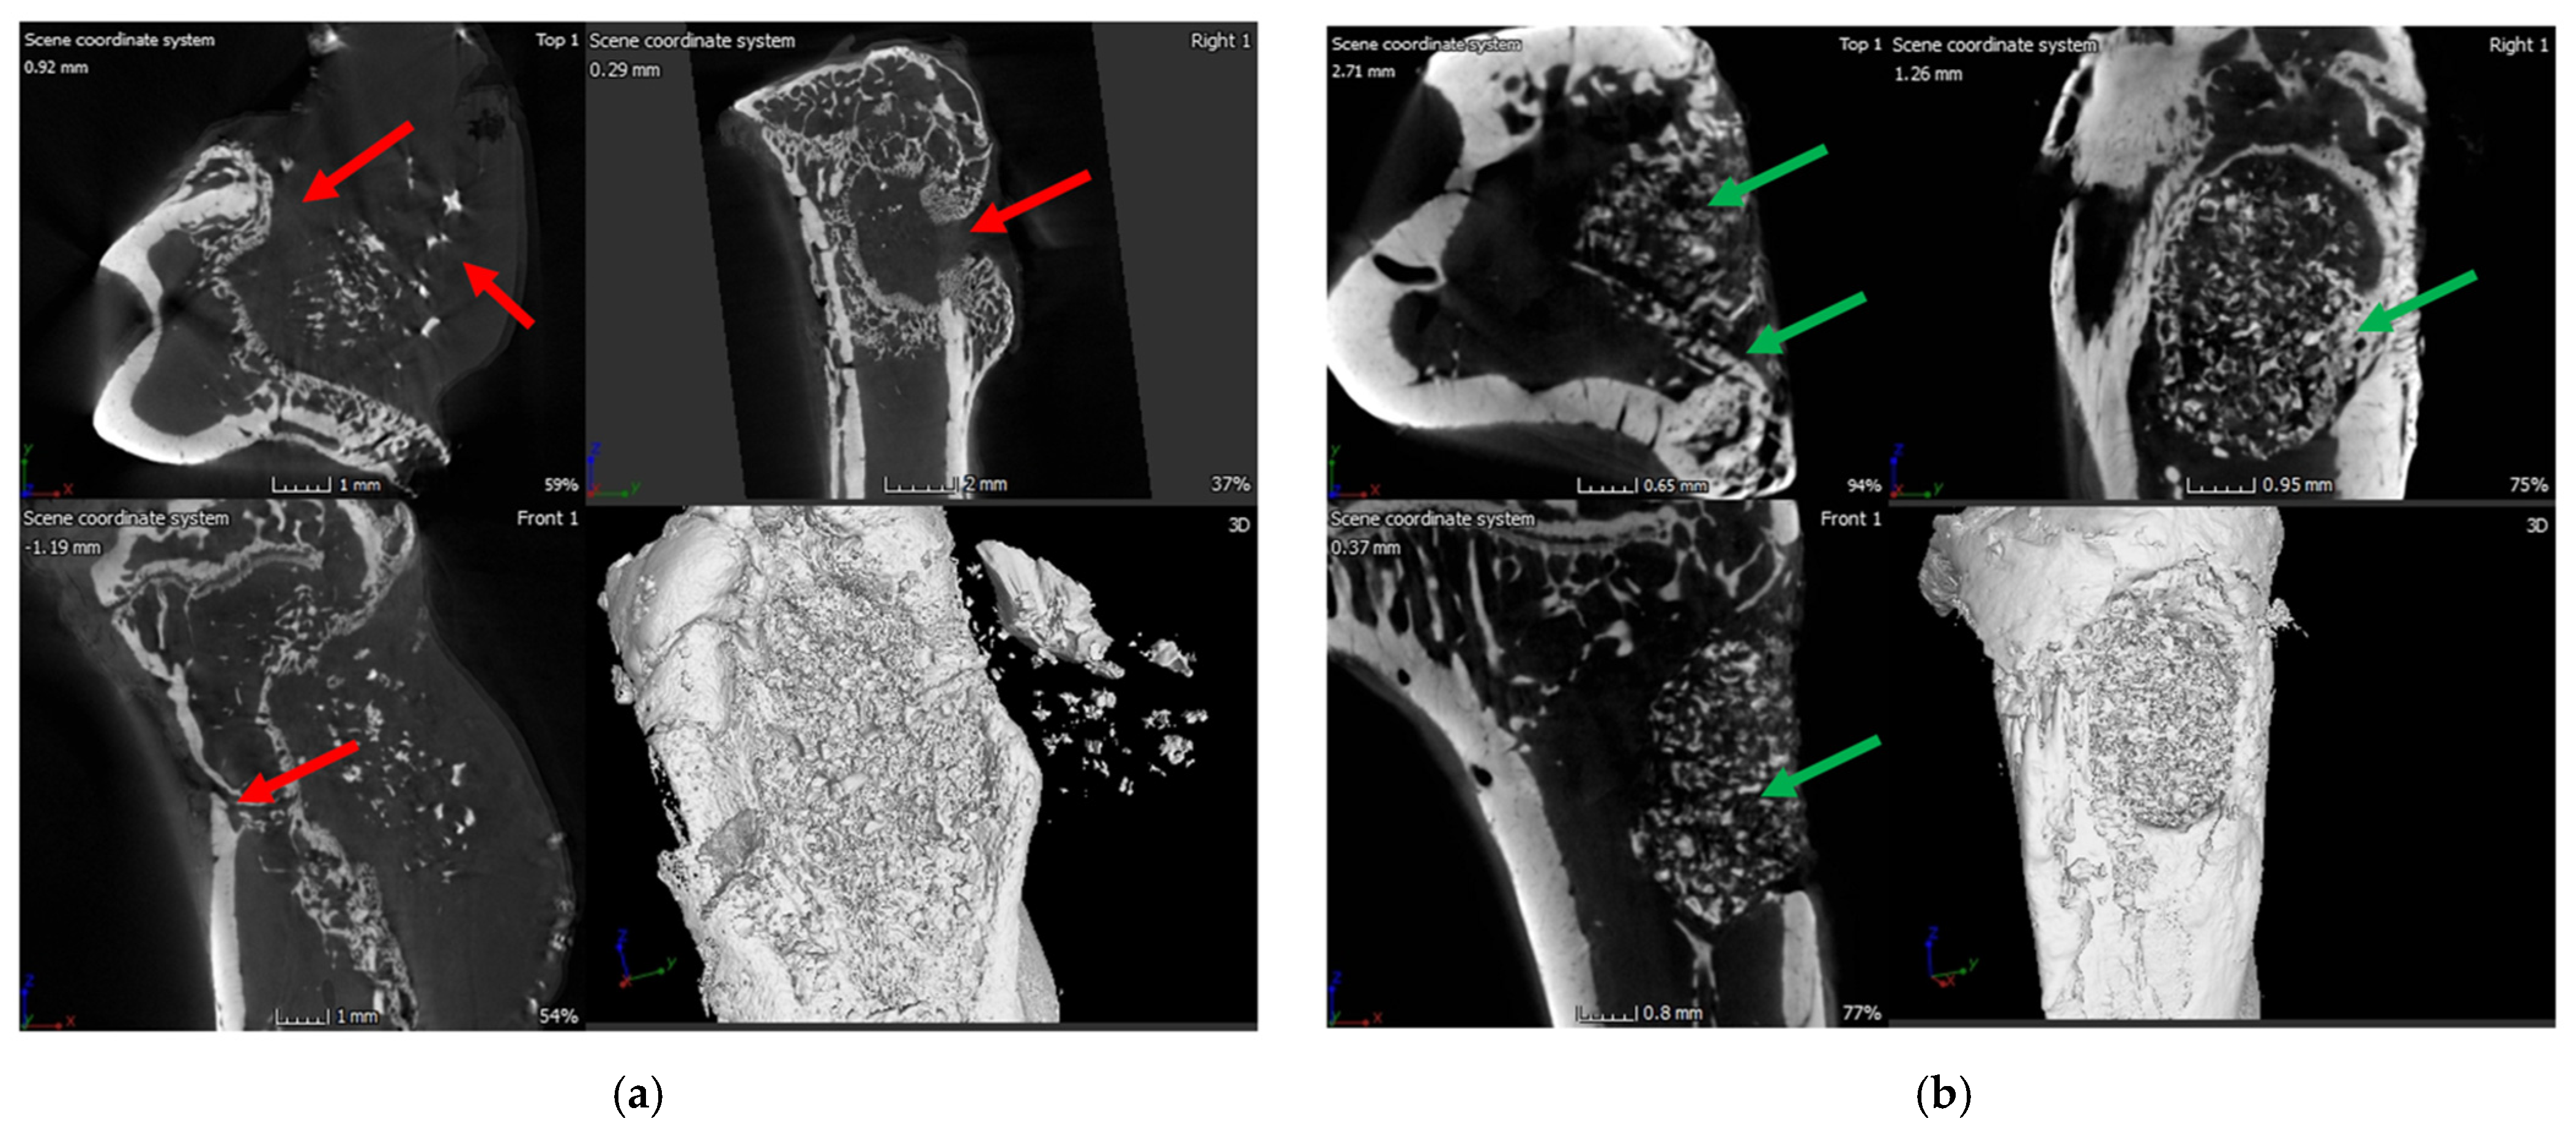

2.6.1. X-ray and μ-CT of Rat Bones

X-ray of the tibia in the infection control group (i.e., BG containing putty with no antibiotic) showed classic signs of infection such as un-healed, osteolytic, and deformed bone (Figure 10). A narrowing of marrow space was also visible. In contrast, the tibia of the treatment group (ABVF-BG putty with vancomycin) showed no signs of infection, and the bone appeared to have healed (Figure 10). μ-CT images showed the presence of infection in the control rat tibia (Figure 11a), including signs of osteomyelitis such as narrowing of the marrow space, the presence of a puss-filled fibrous capsule, sinus tracts, and deformed bone with ectopic bone growth. Alternatively, healing bone without signs of infection was seen in the μ-CT images of tibia from the treatment rats. Specifically, the drilled hole at the surgical site was being filled by immature cancellous and cortical bone (Figure 11b).

Figure 11.

(a) μ-CT images of the rat bone in the infection control group showed signs of infection: narrowing of marrow space, presence of puss-filled fibrous capsule, sinus tract, and deformed bone with ectopic bone growth (red arrows); (b) The treatment group rat bone μ-CT images is showing signs of healing bone as well as the formation of cortical and cancellous bone in the space where the hole was drilled (green arrows).

In spite of the conundrum surrounding our cytotoxicity assay, the in vitro studies indicated the overall safety and efficacy of our ABVF-BG putty; hence, we proceeded to assess our ABVF-BG putty in vivo, with promising results. X-ray imaging showed healed or healing bone in the treatment group (Figure 10b). In contrast, the infection control group showed the telltale signs of osteomyelitis: deformed bone, osteolysis, periosteal thickening, and formation of sequestrum (Figure 10a). The μ-CT of the bones confirmed the findings. The treatment group bone showed no signs of osteomyelitis, as the bone appeared to be healed with new bone formation and remodeling taking place (Figure 11b). On the contrary, severe osteomyelitis was seen in the infection control group with decreased and deformed bone formation, narrowing marrow space, and the formation of sinus tracts. Infection seemed to be spread to the posterior of the bone, and the presence of a puss-filled capsule was also seen (Figure 11a).